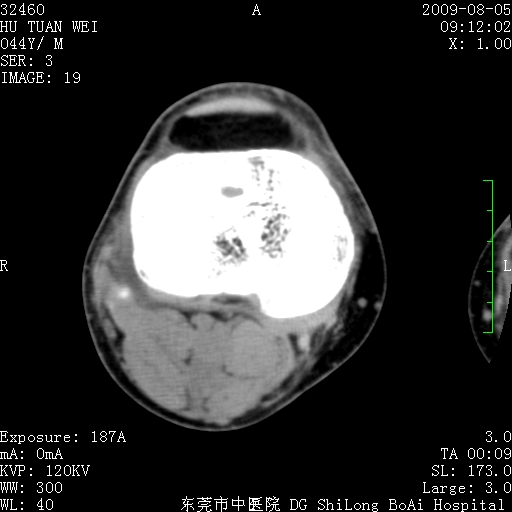

中年男性,膝韧带损伤术前检查!其他病史不清粗,不是我接手病人、且出院了!

1、股骨下段囊状膨胀性病变,边缘硬化明显,内多个残留骨棘呈多房型改变,囊腔密度较高无钙化,膝关节滑膜囊增厚,密度增高,关节腔少量积液。考虑:邻关节囊肿、退变性囊肿(软骨下囊肿)、着色性绒毛结节性滑膜炎、abc、骨巨、良性纤维组织细胞瘤等鉴。虽然年龄偏大,部位于骨端,但有外伤史,本人还是倾向于动脉瘤样骨囊肿(abc)可能性大。邻关节囊肿及软骨下囊肿次之考虑。

2、胫骨髁间棘撕脱骨折,交叉韧带损伤可能;

3、关节退行性改变。

病理结果:色素沉着绒毛结节性滑膜炎

感谢反馈病理结果!本病为慢性关节病变。以关节滑膜高度增生、绒毛结节形成伴含铁血黄素趁着为特点。病因:有炎症、肿瘤、外伤关节出血、代谢障碍、变态反应及感染等学说。增强扫描呈关节腔内单个或多个强化的软组织结节影或滑膜不规则增厚伴关节积液为本病的特征性表现。